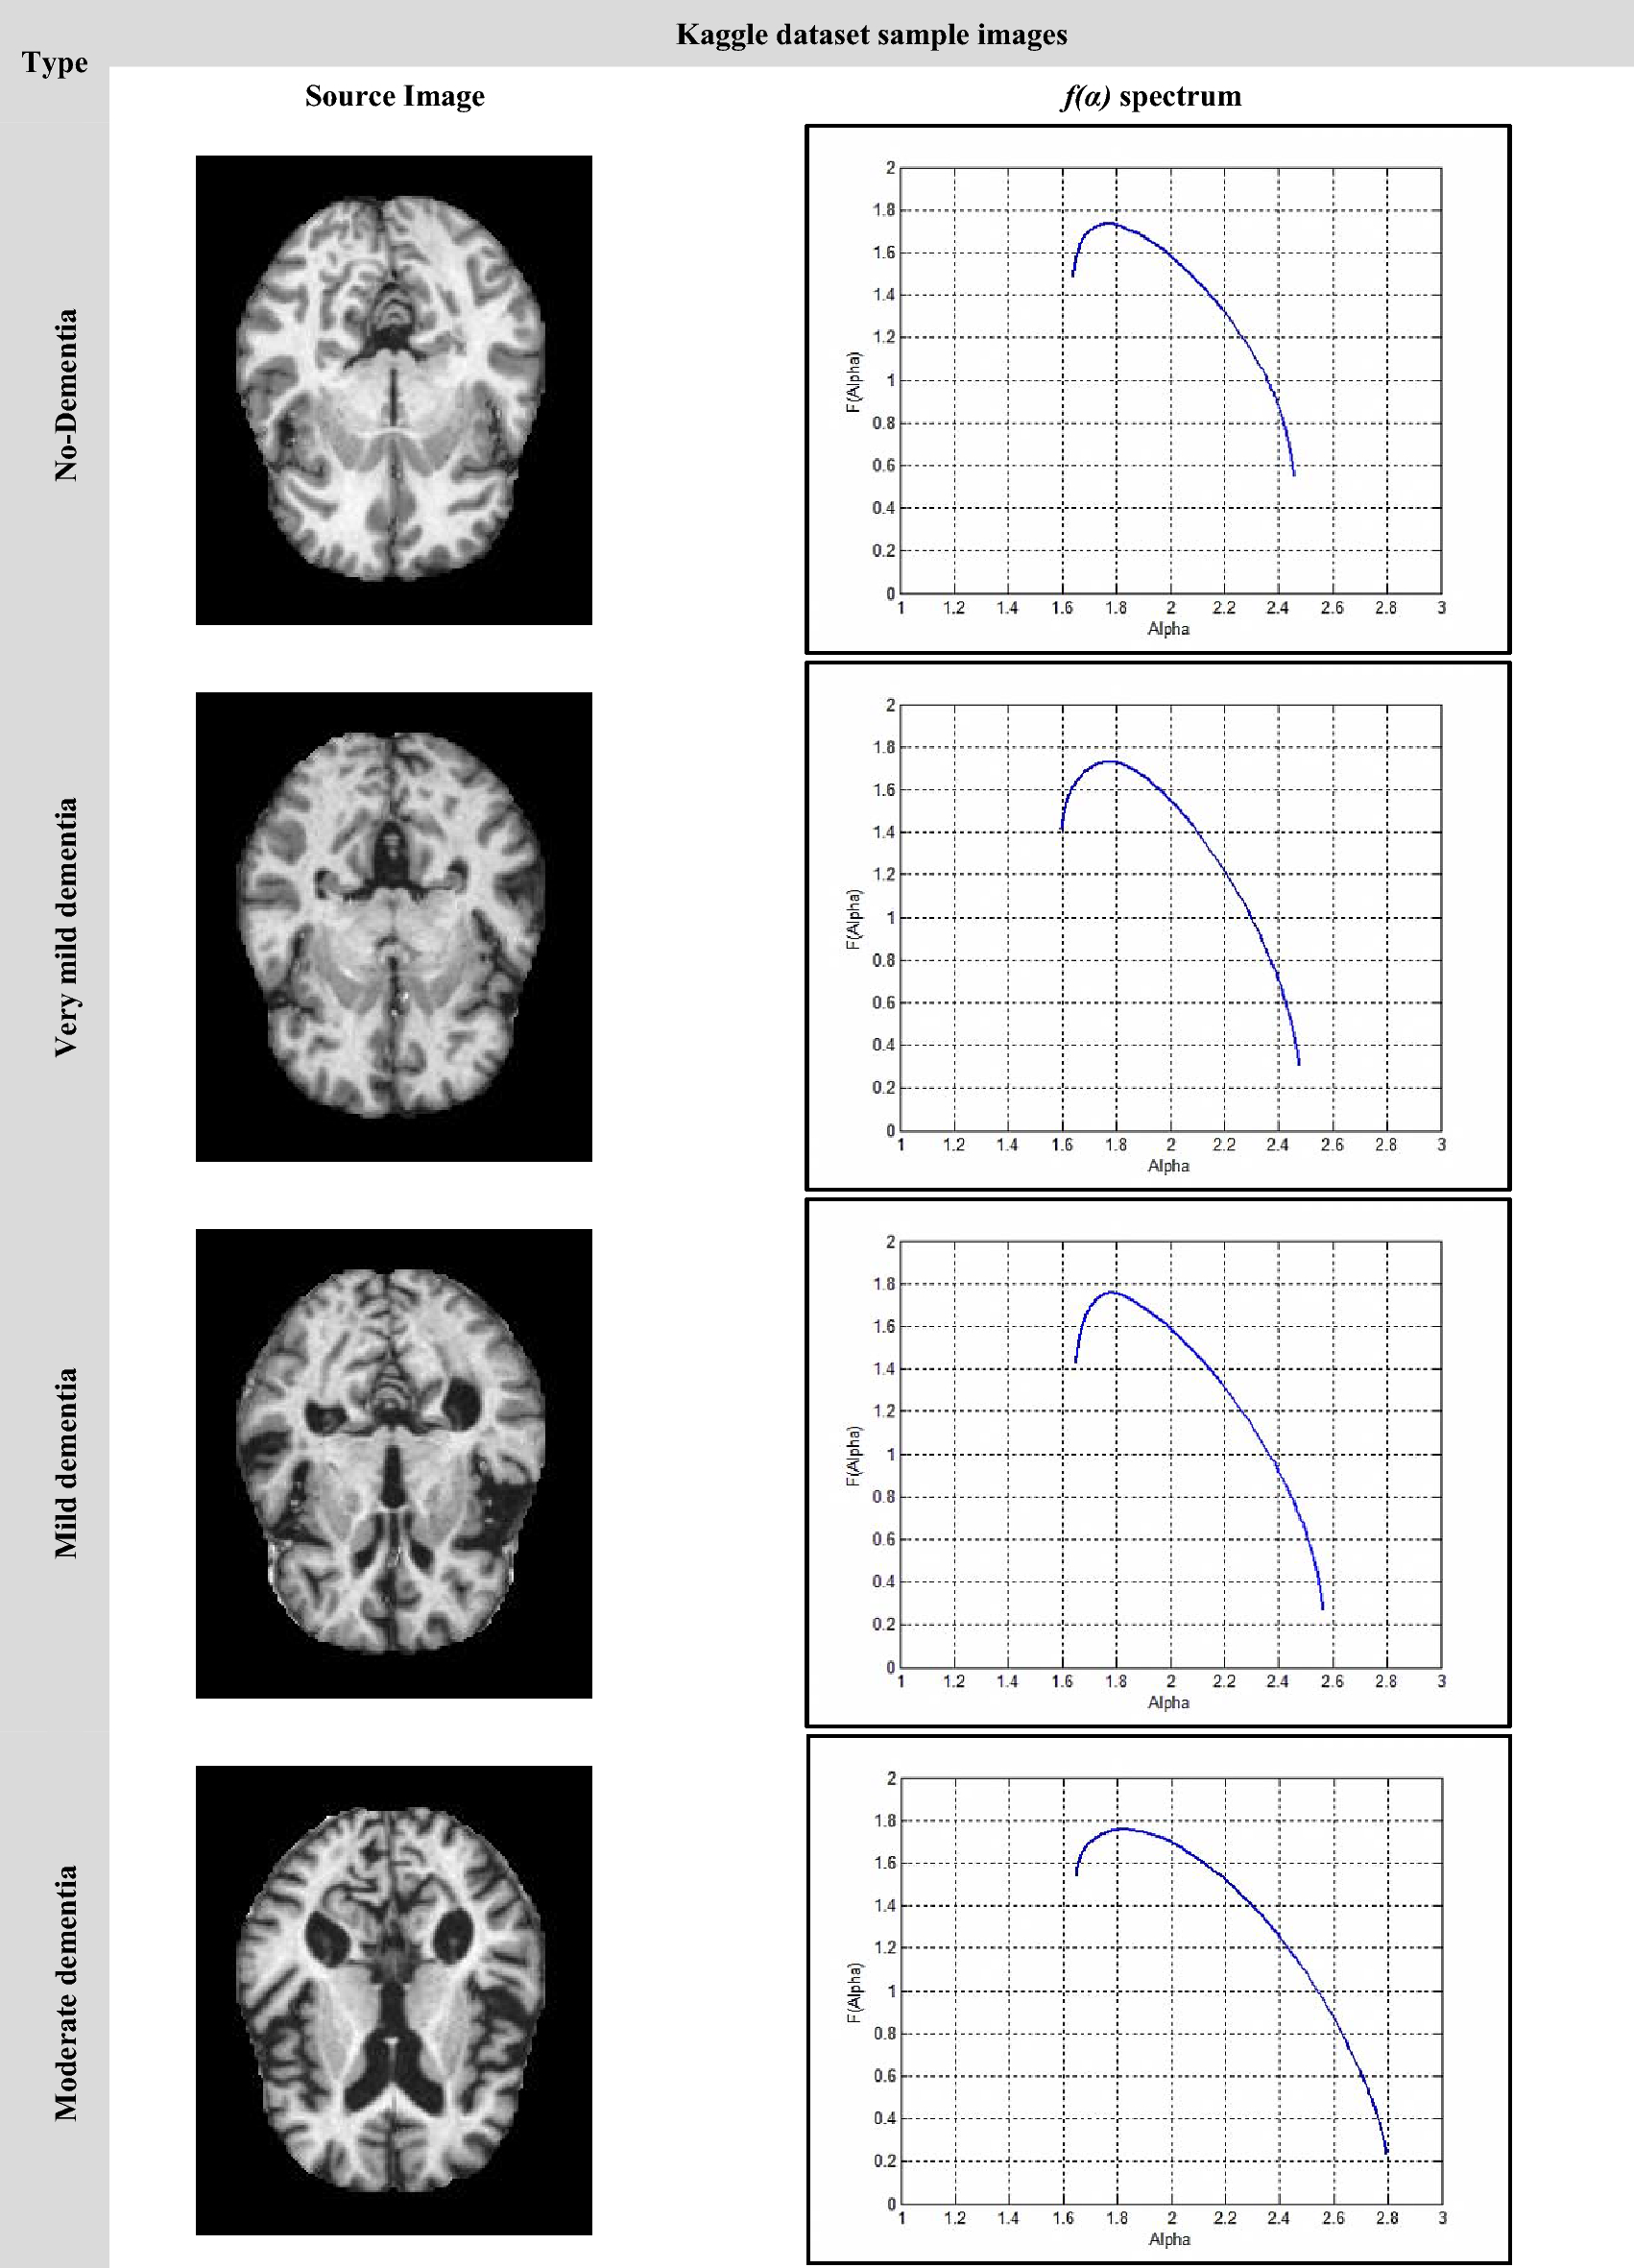

Figure 9

The Kaggle dataset sample images.